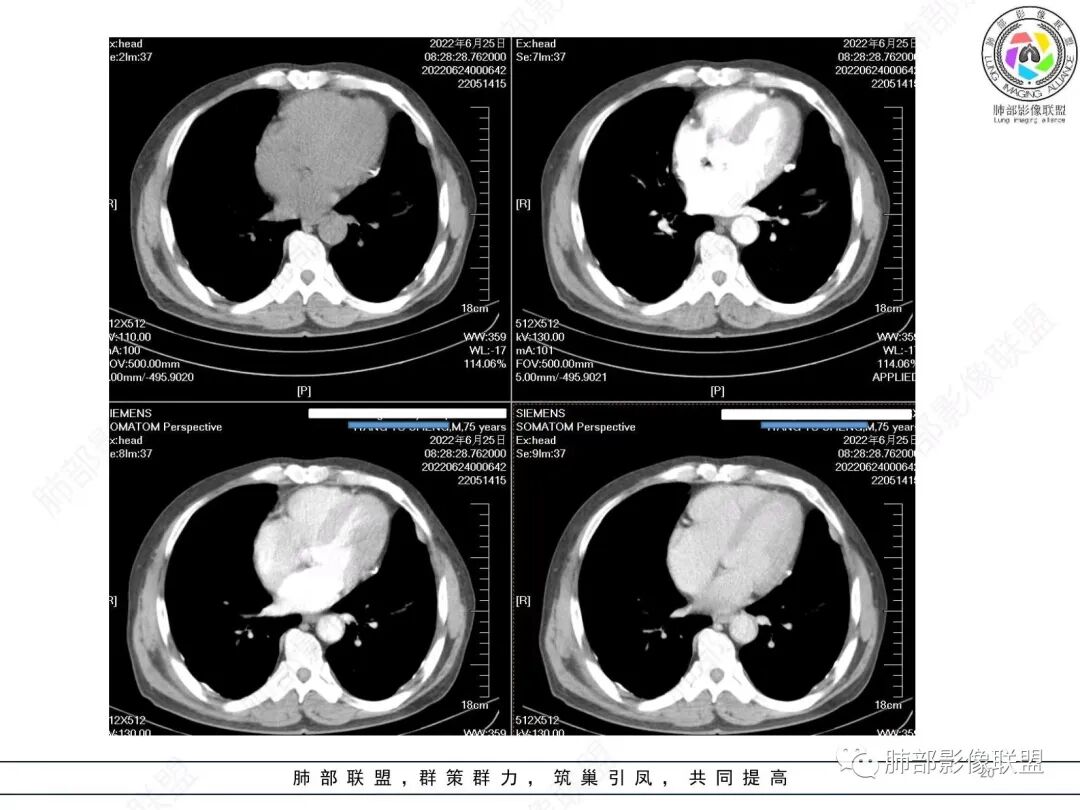

谢加平:

左肺上叶大肿块,膨胀性生长,边界清,密度较低,见部分坏死区,强化弱,肿块见支气管充气V扩张征,分布僵直,枯树枝特点,另一个重要特点血管造影征,淋巴瘤,肿块长轴与胸膜平行,与隐球菌鉴别,隐球荚膜抗原检查,明确诊断经皮肺穿刺。另胸膜钙化(问诊既往有无患胸膜炎病史)。

如果粘液腺Ca,周边太干净了,不支持。

左肺上叶胸膜下肿块,宽基底与胸膜相连,跨叶裂,边缘清晰膨隆,其内支气管充气,部分扩张、僵直,无明显强化,血管造影征,考虑淋巴瘤,鉴别腺癌

左肺胸膜下巨大占位,跨叶裂,宽基底与胸膜相连,胸膜钙化,平扫密度较低,强化不明显,可见内部血管显影,支气管充气征和扩张,考虑为恶性,倾向于淋巴瘤

支持淋巴瘤,左上肺大肿块,有分叶,边缘光整,病灶内密度不均,可见支气管扩张征,增强后可见血管影征。周围肺野清晰。

左肺上叶肿块,宽基底与胸膜相连,跨叶裂,边缘清晰膨隆,可见小分叶,其内支气管充气,部分扩张、僵直,呈枯枝征,支气管达边征,增强无明显强化,可见血管造影征,考虑恶性病变,淋巴瘤,鉴别粘液腺癌。